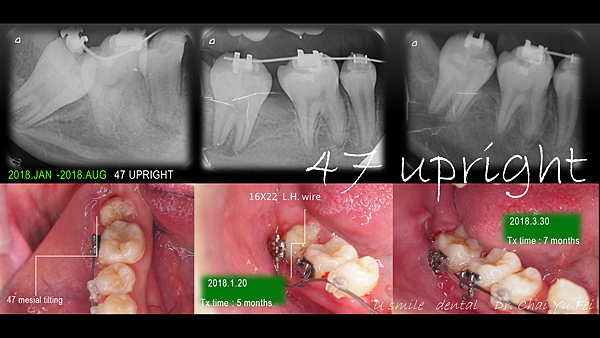

[ 治療方式 ] : 利用LH 線的超彈性將嚴重傾倒的第二大臼齒扶正。

ISW(東京医科歯科大学開発) を使ったので,歯並びを矯正するスピードが速く,三が月ぐらいできれいに並びました.